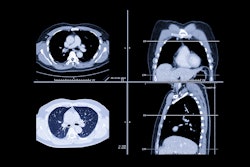

The U.S. Food and Drug Administration (FDA) has granted clearance for U.K. AI software developer Brainomix's 360 e-Lung image processing algorithm.

e-Lung consists of thousands of CT scans from academic institutions, according to the company.